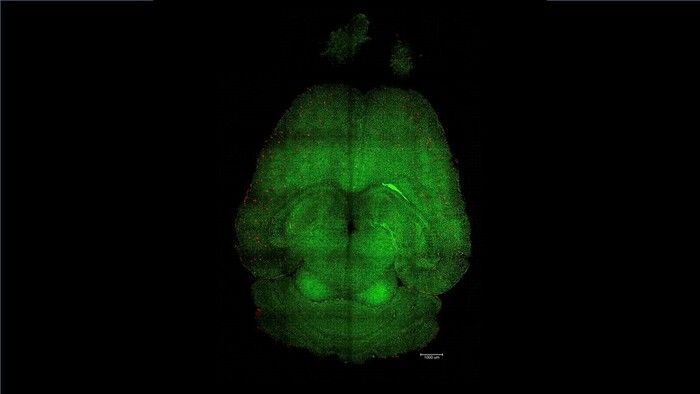

Nanoparticelle che non trasportano molecole terapeutiche ma che sono esse stesse il trattamento hanno fatto regredire la malattia di Alzheimer nei topi : invece di cercare di curare i neuroni, agiscono come interruttori che resettano il sistema vascolare del cervello, permettendogli di riguadagnare la sua capacità di eliminare proteine e altre molecole indesiderate che si accumulano nelle malattie neurodegenerative come Alzheimer e demenza. Il risultato, pubblicato sulla rivista Signal Transduction and Targeted Therapy, si deve al gruppo di ricercatori guidato dall'Istituto di Bioingegneria della Catalogna (Ibec) spagnolo e dal West China Hospital della Sichuan University.

I ricercatori coordinati dall'italiano Giuseppe Battaglia dell'Ibec hanno usato topi geneticamente modificati per produrre maggiori quantità della proteina beta-amiloide e sviluppare così un declino cognitivo simile a quello dell'Alzheimer, e gli hanno somministrato tre dosi di nanoparticelle . Dopo 6 mesi dal trattamento , un animale di 18 mesi, che equivalgono a circa 90 anni di un essere umano, aveva recuperato del tutto il comportamento di un topo sano.

"L'effetto a lungo termine deriva dal ripristino della vascolarizzazione cerebrale ", afferma Battaglia. "Pensiamo che funzioni con un meccanismo a cascata: quando si accumulano specie tossiche come la beta-amiloide la malattia progredisce. Ma una volta che il sistema vascolare è di nuovo in grado di funzionare - sottolinea il ricercatore - inizia a eliminare la beta-amiloide e altre molecole dannose, consentendo all'intero sistema di ritrovare il suo equilibrio ".